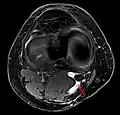

Die Diagnose wird neben der klinisch-manuellen Untersuchung durch Ultraschall (Sonographie) und evtl. eine Kernspintomographie erhärtet; dabei werden auch Differentialdiagnosen wie Aneurysmen der Popliteal-Arterie oder -vene[3] ausgeschlossen.